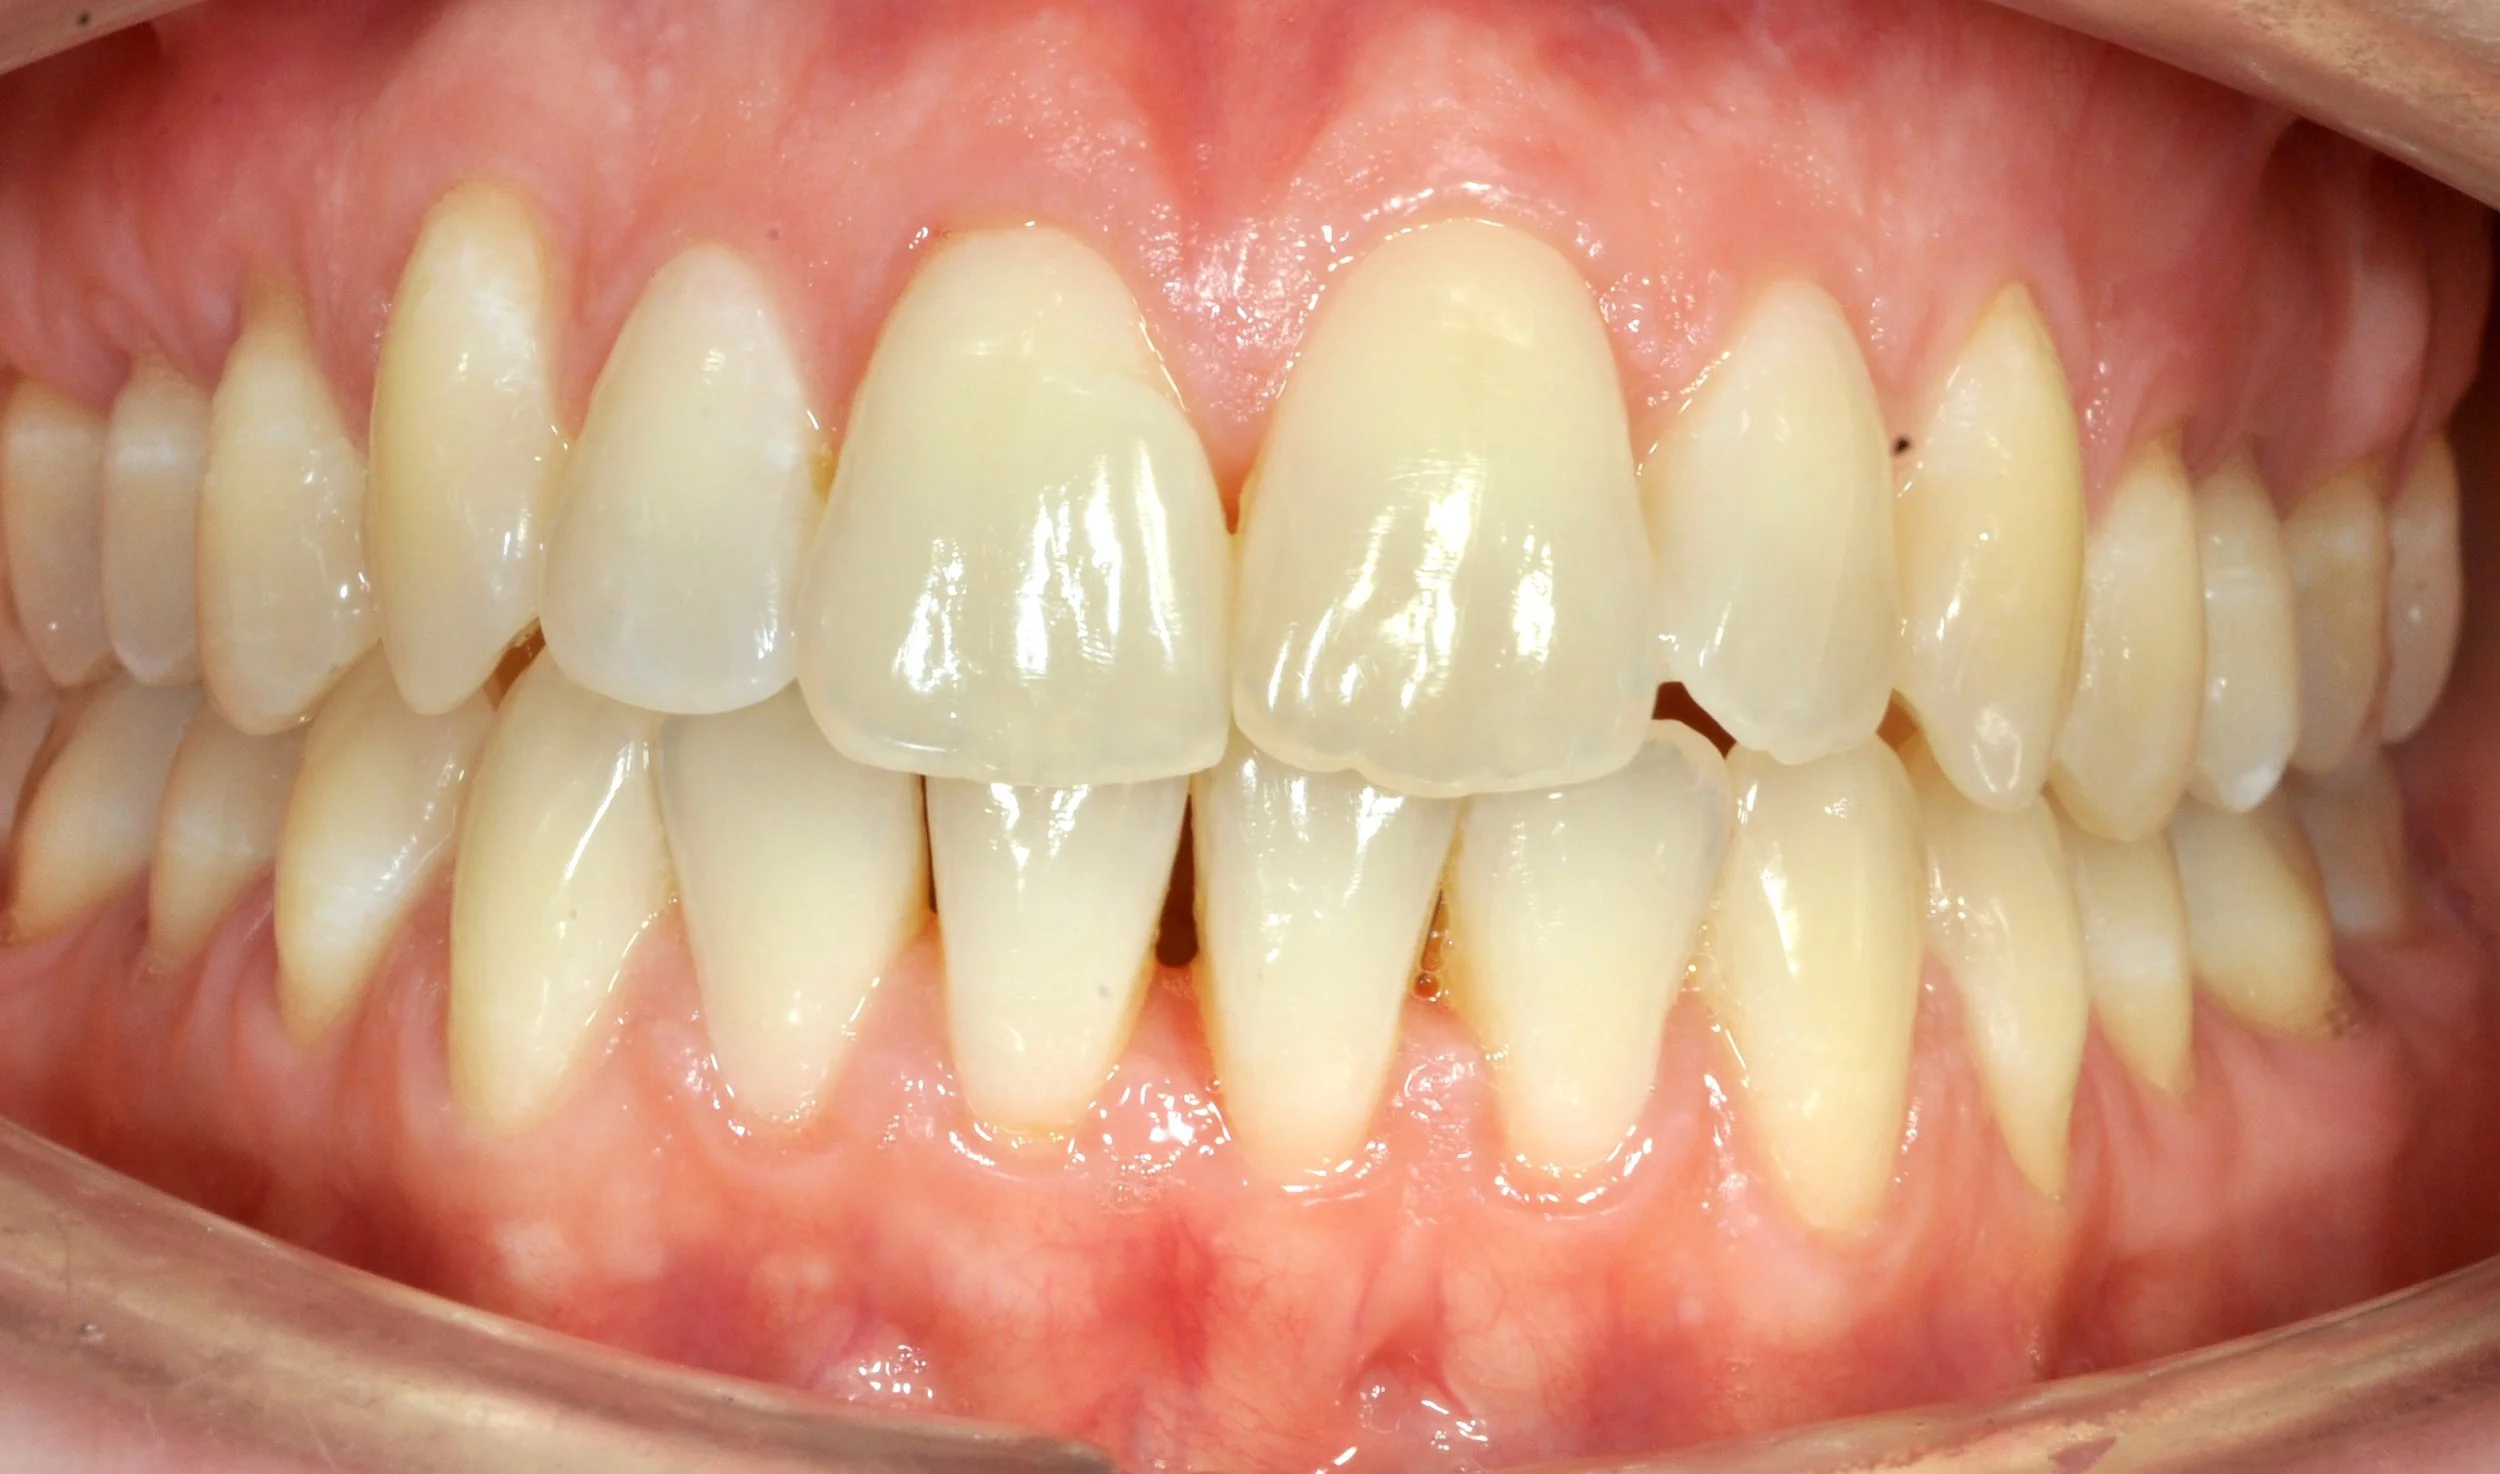

Caso 2 – Allineatori trasparenti in paziente adulto

Paziente adulto con importante affollamento dei denti inferiori, arcate strette e tendenza al morso aperto, con difficoltà nel corretto contatto tra i denti superiori e inferiori.

Il trattamento con allineatori trasparenti ha permesso, in circa 18–20 mesi, di riallineare i denti, ampliare le arcate e migliorare la chiusura del morso, ottenendo un risultato stabile, funzionale ed esteticamente armonioso.

PRIMA

DOPO